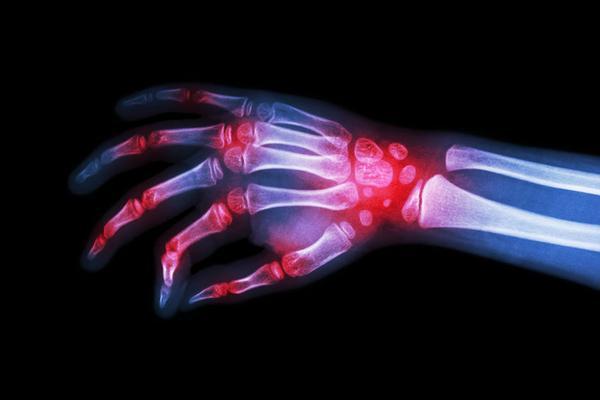

这里要说明的是,痛风的确是以高尿酸血症作为了病发基础,持续升高的血尿酸,会析出一种名为单钠尿酸盐结晶的物质,它们会在患者的关节处沉积,逐渐发展为晶体相关性关节疾病,也就是痛风,其属于代谢性风湿疾病范畴之内。